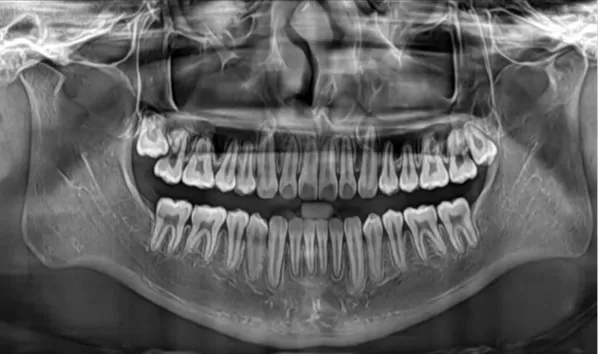

Rayons X avant le traitement

[Radiographie panoramique/Céphalogramme latéral]